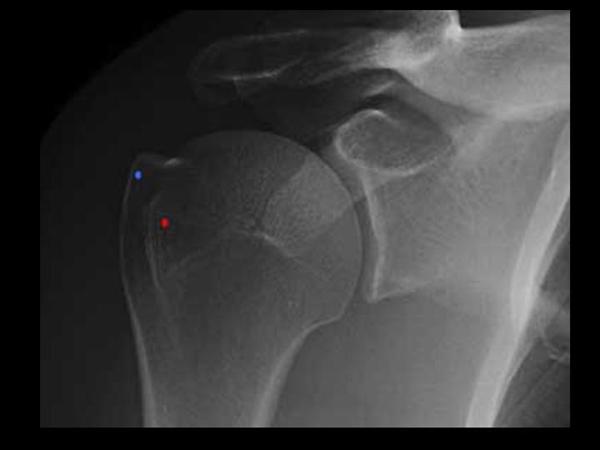

trauma 시에 가장 기본적인 검사는 AP와 axillary lateral view 입니다.

1. shoulder AP

glenohumeral joint space, DJD